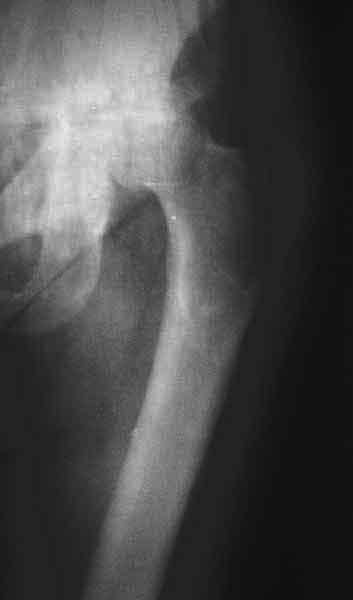

Насчет 8 см согласен с А.Н. Челноковым, это наверное ортопедическое за счет приводящей, сгибательной контрактуры и, возможно, колена. на ликвидацию укорочения у нас обычно уходит около 2-х нед. снимки в приложении, возможно не очень показательные, но других с ходу не нашел, завтра еще поищу.